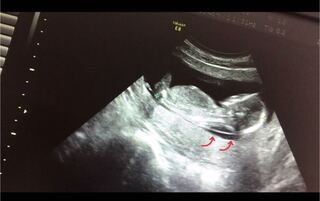

ダウン症とわかるまで その3 妊娠中 後頸部浮腫の指摘 一歩一歩踏みしめて